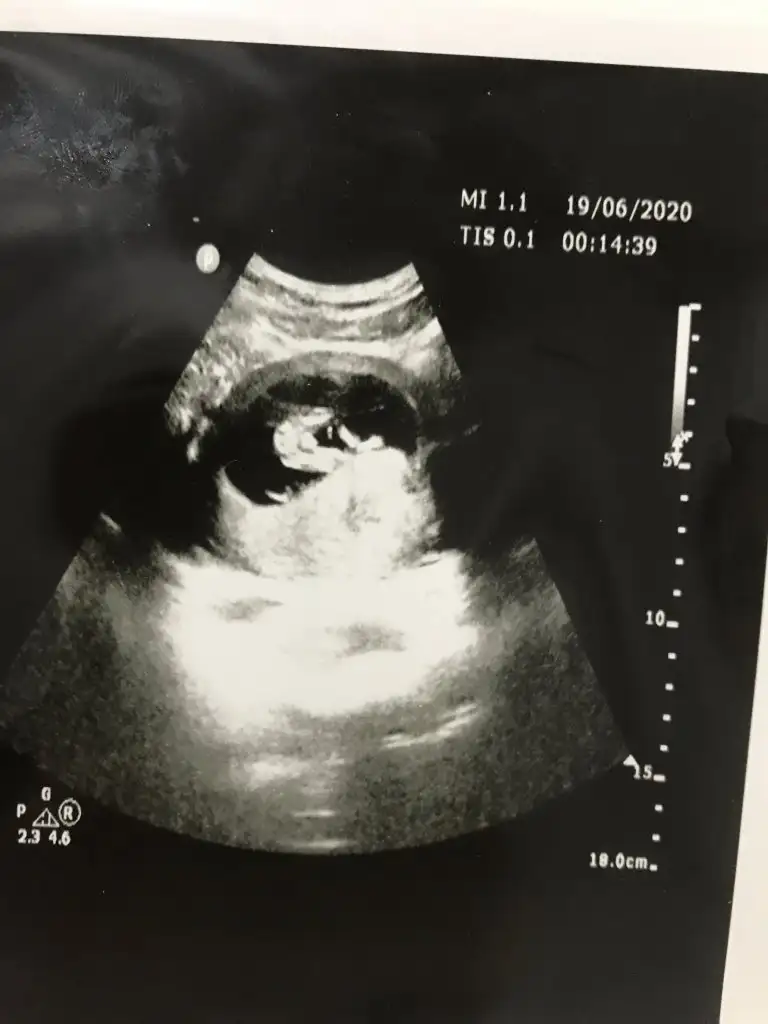

Bunlar net değilBi de bu resimler var.

ÖgrendinizmiEvet net bulamadım en net resmi bu doktor net çekmemiş aslında 12 haftalık teşekkür ederim

Kaç haftalık usg sanki erkek gibi eminde olmadım 11 12 13 haft usgler olmalı tekrar usg paylaşınMerhabalar tahmininizi çok merak ediyorum :)

Üçlü taramada büyük ihtimalle kız olduğu söylendiNet degil usg tek tek çekermisiniz usgler yada başka usg olursa paylaşın 12-13 haftalarda olabilir şimdilik eminde değilim kız gibi gibi emin değilim tekrar usg paylaşın